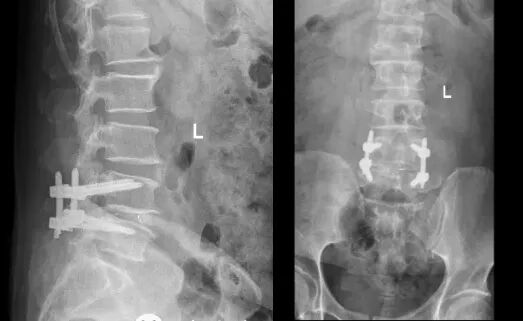

腰椎治疗,挺直人生脊梁

58岁的刘先生反复双下肢麻木,最近一个月尤为严重。知道北京专家要来我院出诊后,便与家属一起来到门诊部,经过初步检查后以“腰椎管狭窄”收入骨一科,继续完善相关检查后诊断为腰椎椎管狭窄症、腰4/5椎间盘突出、腰椎退行性病变。根据病情,北京专家建议手术治疗,经过专家团队的仔细研究和讨论后,决定进行微创经椎间孔腰椎间融合术(MIS-TLIF)。手术顺利,患者非常满意。

术后影像